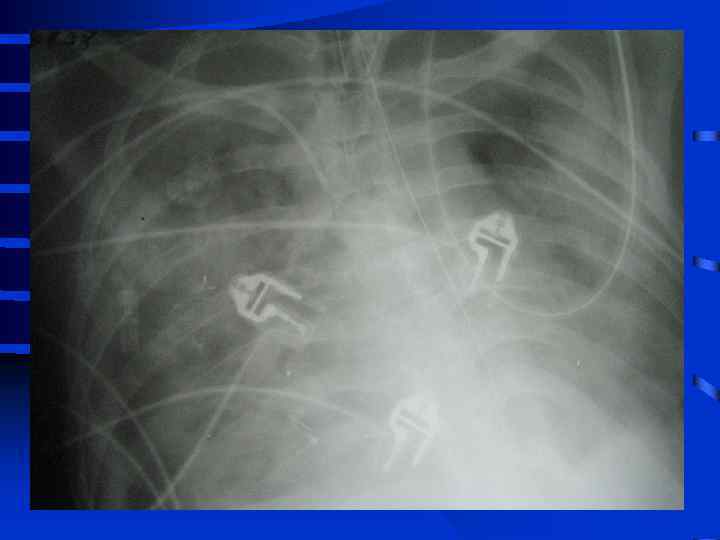

• I стадия Все изменения носят умеренный характер, индекс оксигенации (Pa. O 2/Fi. O 2) более 300, Pa. CO 2 снижен до 34 - 32 мм. рт. ст. , рентгенографически полнокровие легких, ячеистая деформация на фоне усиленного легочного рисунка. • II стадия Повторное, часто резкое ухудшение состояния. Психические нарушения (беспокойство, неадекватность), тахикардия свыше 110 - 120 в мин. , АД сист. более 150 мм. рт. ст. , индекс оксигенации менее 250 - 200, артериальная гипокапния. Рентгенографически - появление мелкоочаговых теней на периферии

• III стадия необходима респираторная поддержка, сознание нарушено, индекс оксигенации менее 200, шунтирование 30 - 50% от величины МОК. Появляются признаки полиорганного поражения: нарушение функции кишечника (парезы, острые язвы) • и почек (эпизоды олигурии) • Рентгенографически - сливные тени, иногда первые признаки гидроторакса

• IV стадия появляются симптомы присоединения инфекции с развитием гнойного трахеобронхита и пневмонии (госпитальной), признаки сепсиса, вторая волна полиорганной недостаточности. Индекс оксигенации менее 100, появляется гиперкапния. Рентгенографически - резкое снижение прозрачности легочных полей, множественные хлопьевидные тени (“снежная буря”).

Объективные признаки развития ОРДС • 1. Индекс оксигенации снижен • 2. Симметричные рентгенографические изменения инфильтративного характера • 3. Увеличение внутрилегочного шунта (более 25% от величины МОК) • 4. Возрастание альвеолярно-артериальной разницы по кислороду (более 250 мм. рт. ст. при Fi. O 2 = 1, 0) • 5. Легочная гипотензия (PCWP не более 12 мм. рт. ст. ) • 6. Уменьшение растяжимости (податливости) легких 50 мл/см. вод. ст. и менее

Тяжесть ОРДС по J. Murray (1988) • А) Рентгенография (инфильтрация от 0 до 4 квадрантов = 0 - 4 балла • Б) Гипоксия (PAO 2/Fi. O 2) от 300 и выше до 100 и менее = 0 - 4 балла • В) Растяжимость легких (от 80 и более до 20 и менее мл/см. вод. ст. ) = 0 - 4 балла • Г) ПДКВ при ИВЛ (от 0 до 14 см. вод. ст. и выше) = 0 - 4 балла • К от 0, 1 до 2, 5 - умеренное повреждение, более 2, 5 - тяжелое